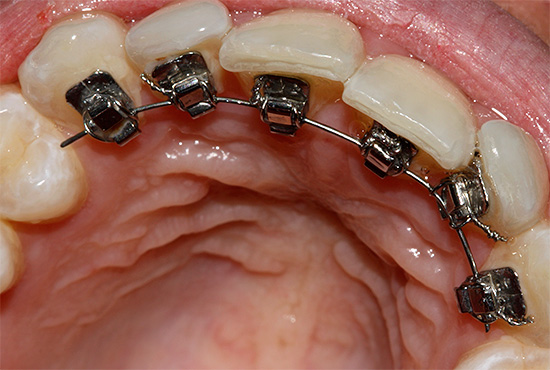

L'uso del sistema a staffa nel trattamento della malocclusione è il metodo di scelta (anche in età adulta). Che cos'è un sistema di staffe? In termini semplici, le parentesi graffe sono dispositivi fissi fissati ai denti, con blocchi, in cui è incorporato un programma speciale per lo spostamento dei denti. Il movimento viene eseguito a causa dell'arco, che è fissato in questi blocchi, l'arco si muove e raggiunge la forma ideale dell'arco dentale.

- parentesi graffe, ovvero, l'arco è legato alla staffa mediante speciali legature in metallo o gomma. Le legature forniscono una rigida adesione dell'arco alla staffa e limitano lo scorrimento lungo l'arco dentale. Lo svantaggio di questa attrezzatura è la necessità di frequenti visite dal medico una volta al mese (e alcuni medici prescrivono i pazienti ogni due settimane). Le visite sono necessarie per sostituire le legature, poiché tendono a indebolirsi.

- I sistemi di staffe auto-leganti differiscono dai precedenti in quanto il design della staffa ha un coperchio che trattiene l'arco all'interno della serratura. Ciò fornisce uno scorrimento più libero dell'arco metallico lungo la dentatura, che è più comodo per il paziente, riduce il numero di visite dal medico e il tempo di trattamento. Ma tali apparecchi sono più costosi dei sistemi di legatura.

- Bretelle linguali: questo tipo di parentesi graffe viene riparato dal medico sul lato linguale dei denti. Pertanto, non sono visibili agli altri. Tuttavia, quando si indossano tali apparecchi, sorgono alcune difficoltà: irritazione costante della lingua, dizione alterata. Le parentesi graffe linguali richiedono cure e igiene più accurate rispetto alle parentesi graffe convenzionali. Il medico ordina l'intero set individualmente per ciascun paziente e, di conseguenza, se la staffa o l'arco si rompono, allora ci saranno difficoltà con la riparazione e la sostituzione, poiché gli archi e le parentesi graffe di altri sistemi non funzioneranno in questo caso. Il costo del trattamento con apparecchi ortodontici è molto più elevato rispetto ai sistemi convenzionali.

È importante mantenere un buon livello di igiene durante il trattamento delle parentesi graffe, lavarsi i denti dopo ogni pasto e utilizzare set di spazzole per pulire l'area intorno alla staffa, tra l'arco e i denti, oltre al pennello. Se trascuri l'igiene, è possibile la formazione di macchie bianche sui denti - focolai di demineralizzazione dello smalto al posto delle parentesi graffe, tali punti stessi non passano in futuro e richiedono un trattamento.